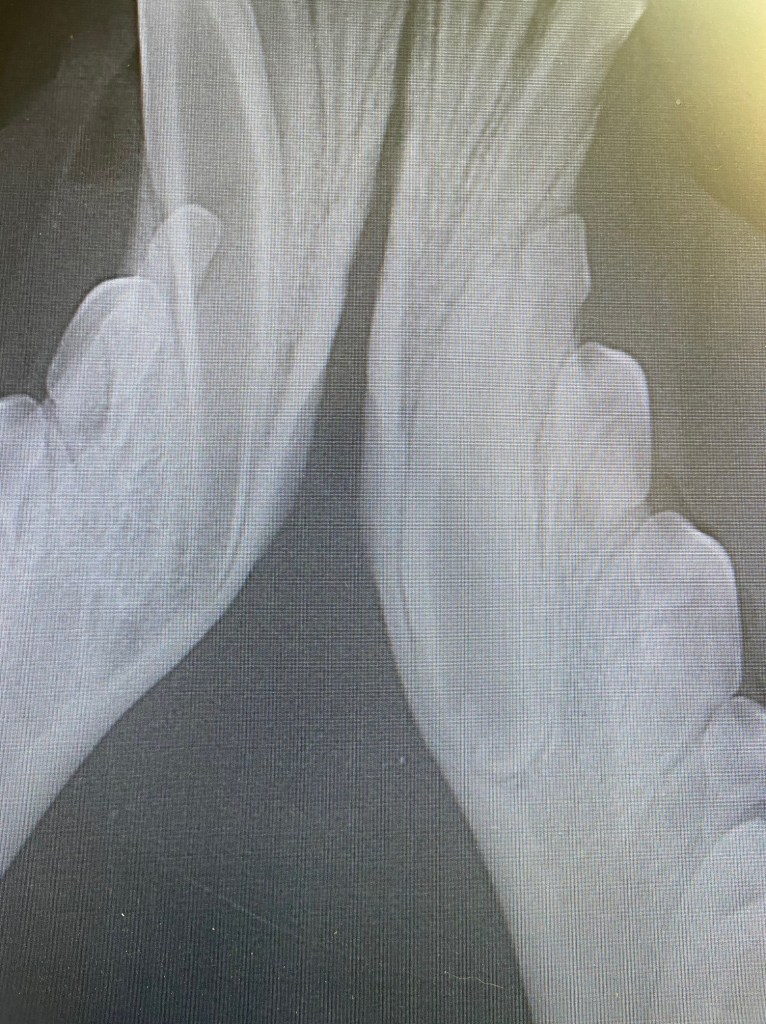

Abnormal crown structure of retained canine

The retained canine tooth with very wide root and abnormal crown